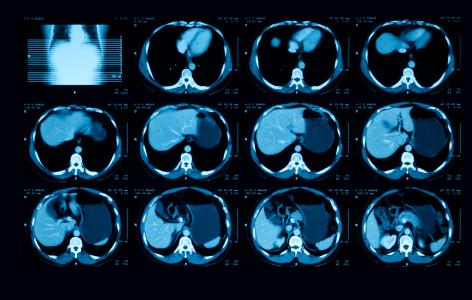

Le carcinome urothélial représente environ 90% des cancers de la vessie et son incidence est d'environ 70.000 nouveaux cas entraînant 17.000 décès par an aux États-Unis. Lorsqu’il est avancé, le carcinome urothélial est inopérable et est normalement traité avec des médicaments de chimiothérapie à base de platine, tels que le cisplatine ou le carboplatine, et/ou des médicaments inhibiteurs de point de contrôle immunitaire qui visent à libérer les capacités anticancéreuses du système immunitaire. Mais dans la plupart des cas, ces traitements fonctionnent pendant une période limitée avant que la maladie ne se remette à progresser.

Le sacituzumab govitecan est un conjugué anticorps-médicament. La partie médicamenteuse, un agent de chimiothérapie appelé SN-38, est attachée à un anticorps qui se concentre sur un récepteur appelé Trop-2, présent sur la plupart des cellules de carcinome urothélial. De cette façon, le médicament peut cibler spécifiquement les cellules tumorales tout en épargnant largement les cellules saines.